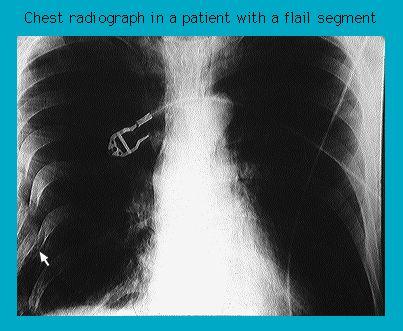

Chest radiograph of a flail chest